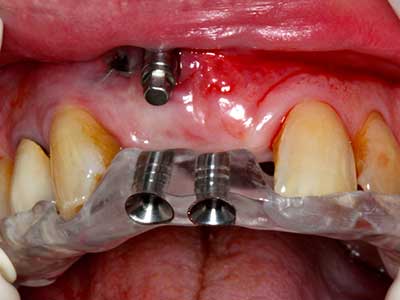

Indikation: Bone Splitting

Knochengewebe ist nicht nur rein mineralisch, sondern auch in wesentlichen Anteilen aus Kollagenfasern aufgebaut. Dies gewährleistet neben einer guten Druckfestigkeit eine gewisse Flexibilität, welche für die Durchführung von Augmentationen genutzt werden kann. Bei der klassischen Expansionsplastik im Sinne eines Bone Splittings wird der atrophierte Kieferkamm in seiner Längsachse gespalten und nach Erreichen einer ausreichenden Osteotomietiefe vorsichtig aufgedehnt (Abb. 13-16), idealerweise ohne den Kiefer wesentlich zu deperiostieren (Brugnami, Caiazzo et al. 2014, Stricker, Fleiner et al. 2014). Bewährt haben sich Schrauben- und Plattensysteme mit zunehmender Expansionsdistanz, um die beiden Knochenlamellen unterhalb der Bruchschwelle voneinander zu distanzieren. In der Regel werden Restknochenbreiten von mindestens 3-4 mm gefordert (Chiapasco, Zaniboni et al. 2006), um eine ausreichende Flexibilität und knöcherne Bedeckung der einzubringenden Implantate zu gewährleisten. Ggf. kann eine ein- oder beidseitige vertikale Entlastungsosteotomie die Flexibilität verbessern. Als Alternative zur klassischen Technik wurde eine Kombination mit weiteren augmentativen Techniken vor allem auf der bukkalen Seite beschrieben.

Mittels Piezosägen erfolgt die Anlage des Splittings besonders schonend und ohne wesentliche Dimensionsverluste, so dass sich keine signifikanten Unterschiede von Implantaten im gesplitteten Kiefer im Vergleich zum nicht defizitären Alveolarkamm gezeigt haben (Chiapasco, Zaniboni et al. 2006, Danza, Guidi et al. 2009). Gerade beim lokal begrenzten und tiefen Splitting ist jedoch stets auf eine ausreichende Wasserkühlung zu achten, um thermische Belastungen in den apikalen Osteotomiebereichen zu vermeiden.